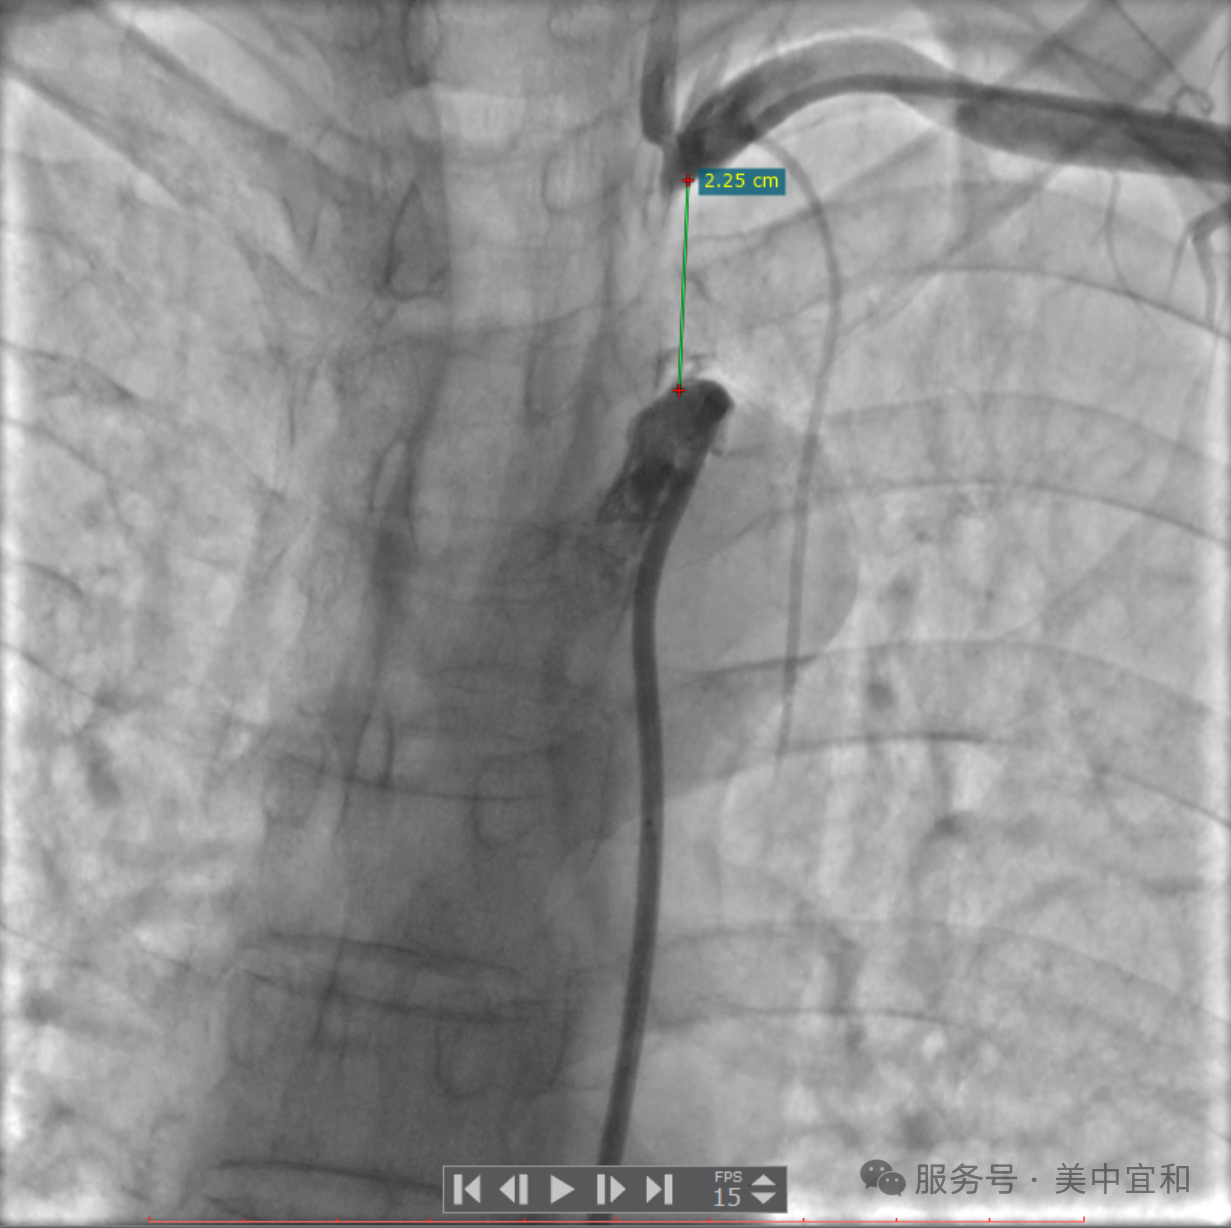

明确诊断后,经过心内科团队的反复讨论,为患者制定了缜密的介入治疗计划。最终,经过近 2 个多小时的手术,成功逆向开通血管并植入支架,术后患者双上肢血压恢复一致,左侧椎动脉供血良好,眩晕症状明显改善,悬着的心也终于放下了。